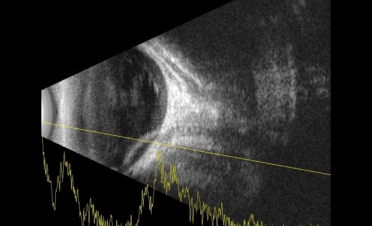

Se le realizó una ecografía y una retinografía para confirmar el diagnóstico.

La ecografía permite observar las estructuras del globo ocular cuando la transparencia de la córnea está comprometida o cuando deseamos observar con detalle los segmentos anterior y posterior del ojo.

En ambas pruebas se observaron imágenes compatibles con un desprendimiento de retina:

Imágenes de la ecografía de Fox, un perro de raza Pomerania con desprendimiento de retina en ambos ojos. Se descartaron otro tipo de lesiones oculares. Foto: IVO. (Clicar la fotografía para ampliar)